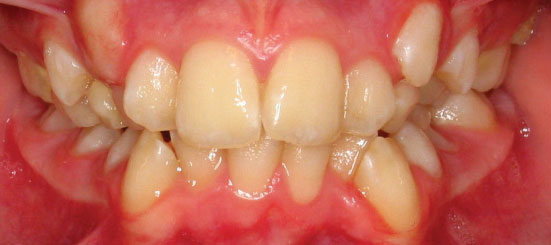

Class I Non-Extraction |